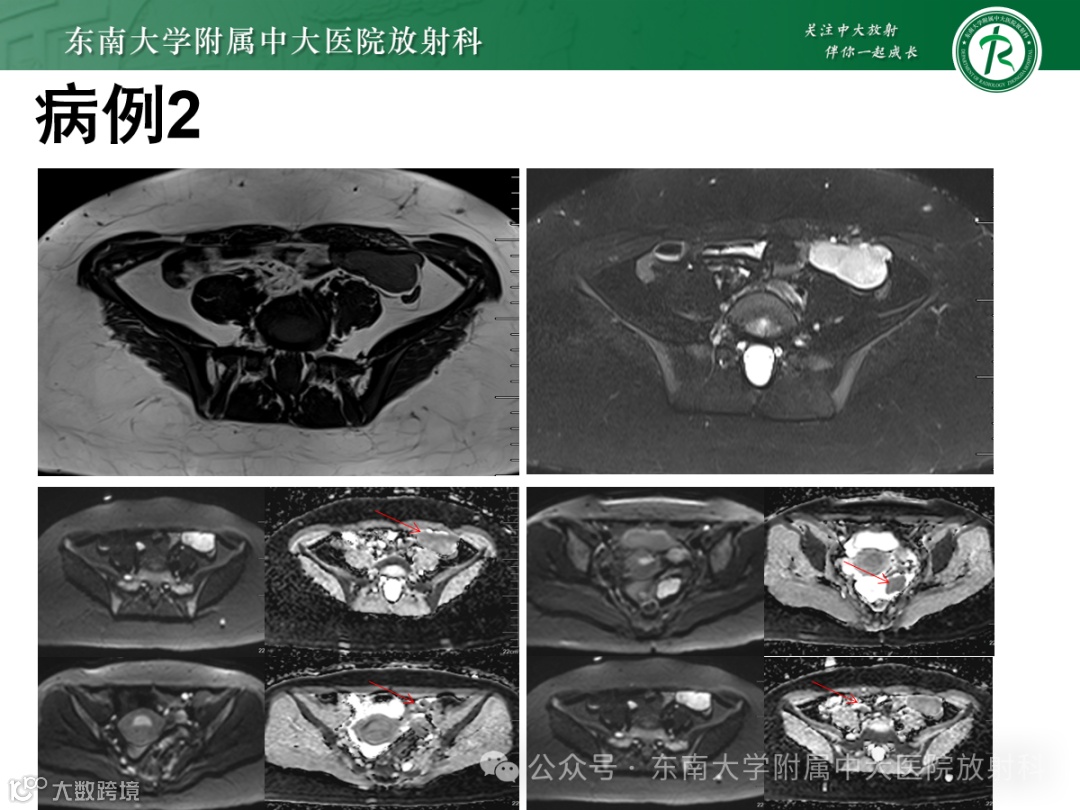

女 ,69岁 主诉:发现盆腔包块 1 天

现病史:患者53岁自然绝经,无异常阴道流血、流液。1 天前于我院体检发现盆腔包块,查阴道B超:右侧附件区见一囊性包块,大小:8.2cm×6.7cm×7.6cm,外形尚规则,界尚清,壁厚 0.24cm,内部透声差,见散在小颗粒样中高回声,见数条分隔带,CDFI:囊壁上见少量血流信号

有尿频尿急,无腹痛腹胀,无腰酸。实验室检查无异常